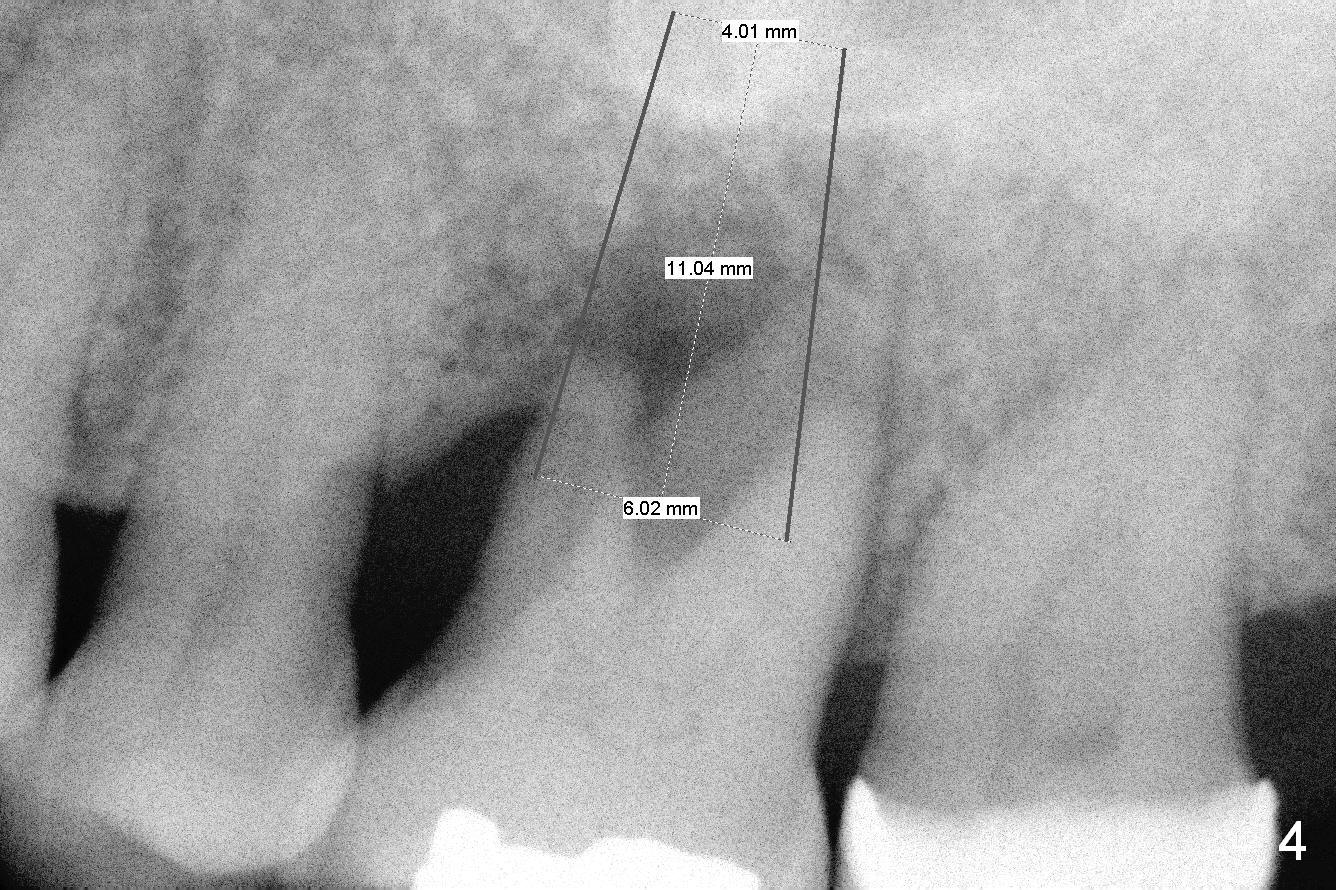

A 54-year-old woman has history of chronic periodontitis with bruxism. Bone loss at the tooth #14 starts at the mesial crest (Fig.1: 2008), extends to the mesial root (Fig.2, 2015) and the palatal one (Fig.3, 2016). The periodontal pockets are deep with mobility III. Since the defect is large with low bone density, Magic osteotomes are going to be used for CMC immediately after extraction (Clindamycin). If there is no history of sinusitis, a 11 mm long implant will be placed (Fig.4). Allograft (.5-1.5 mm) will be delivered with the large bone carrier for CMC (prior to implant placement) and the amalgam carriers for socket gap closure (before and after implant placement).